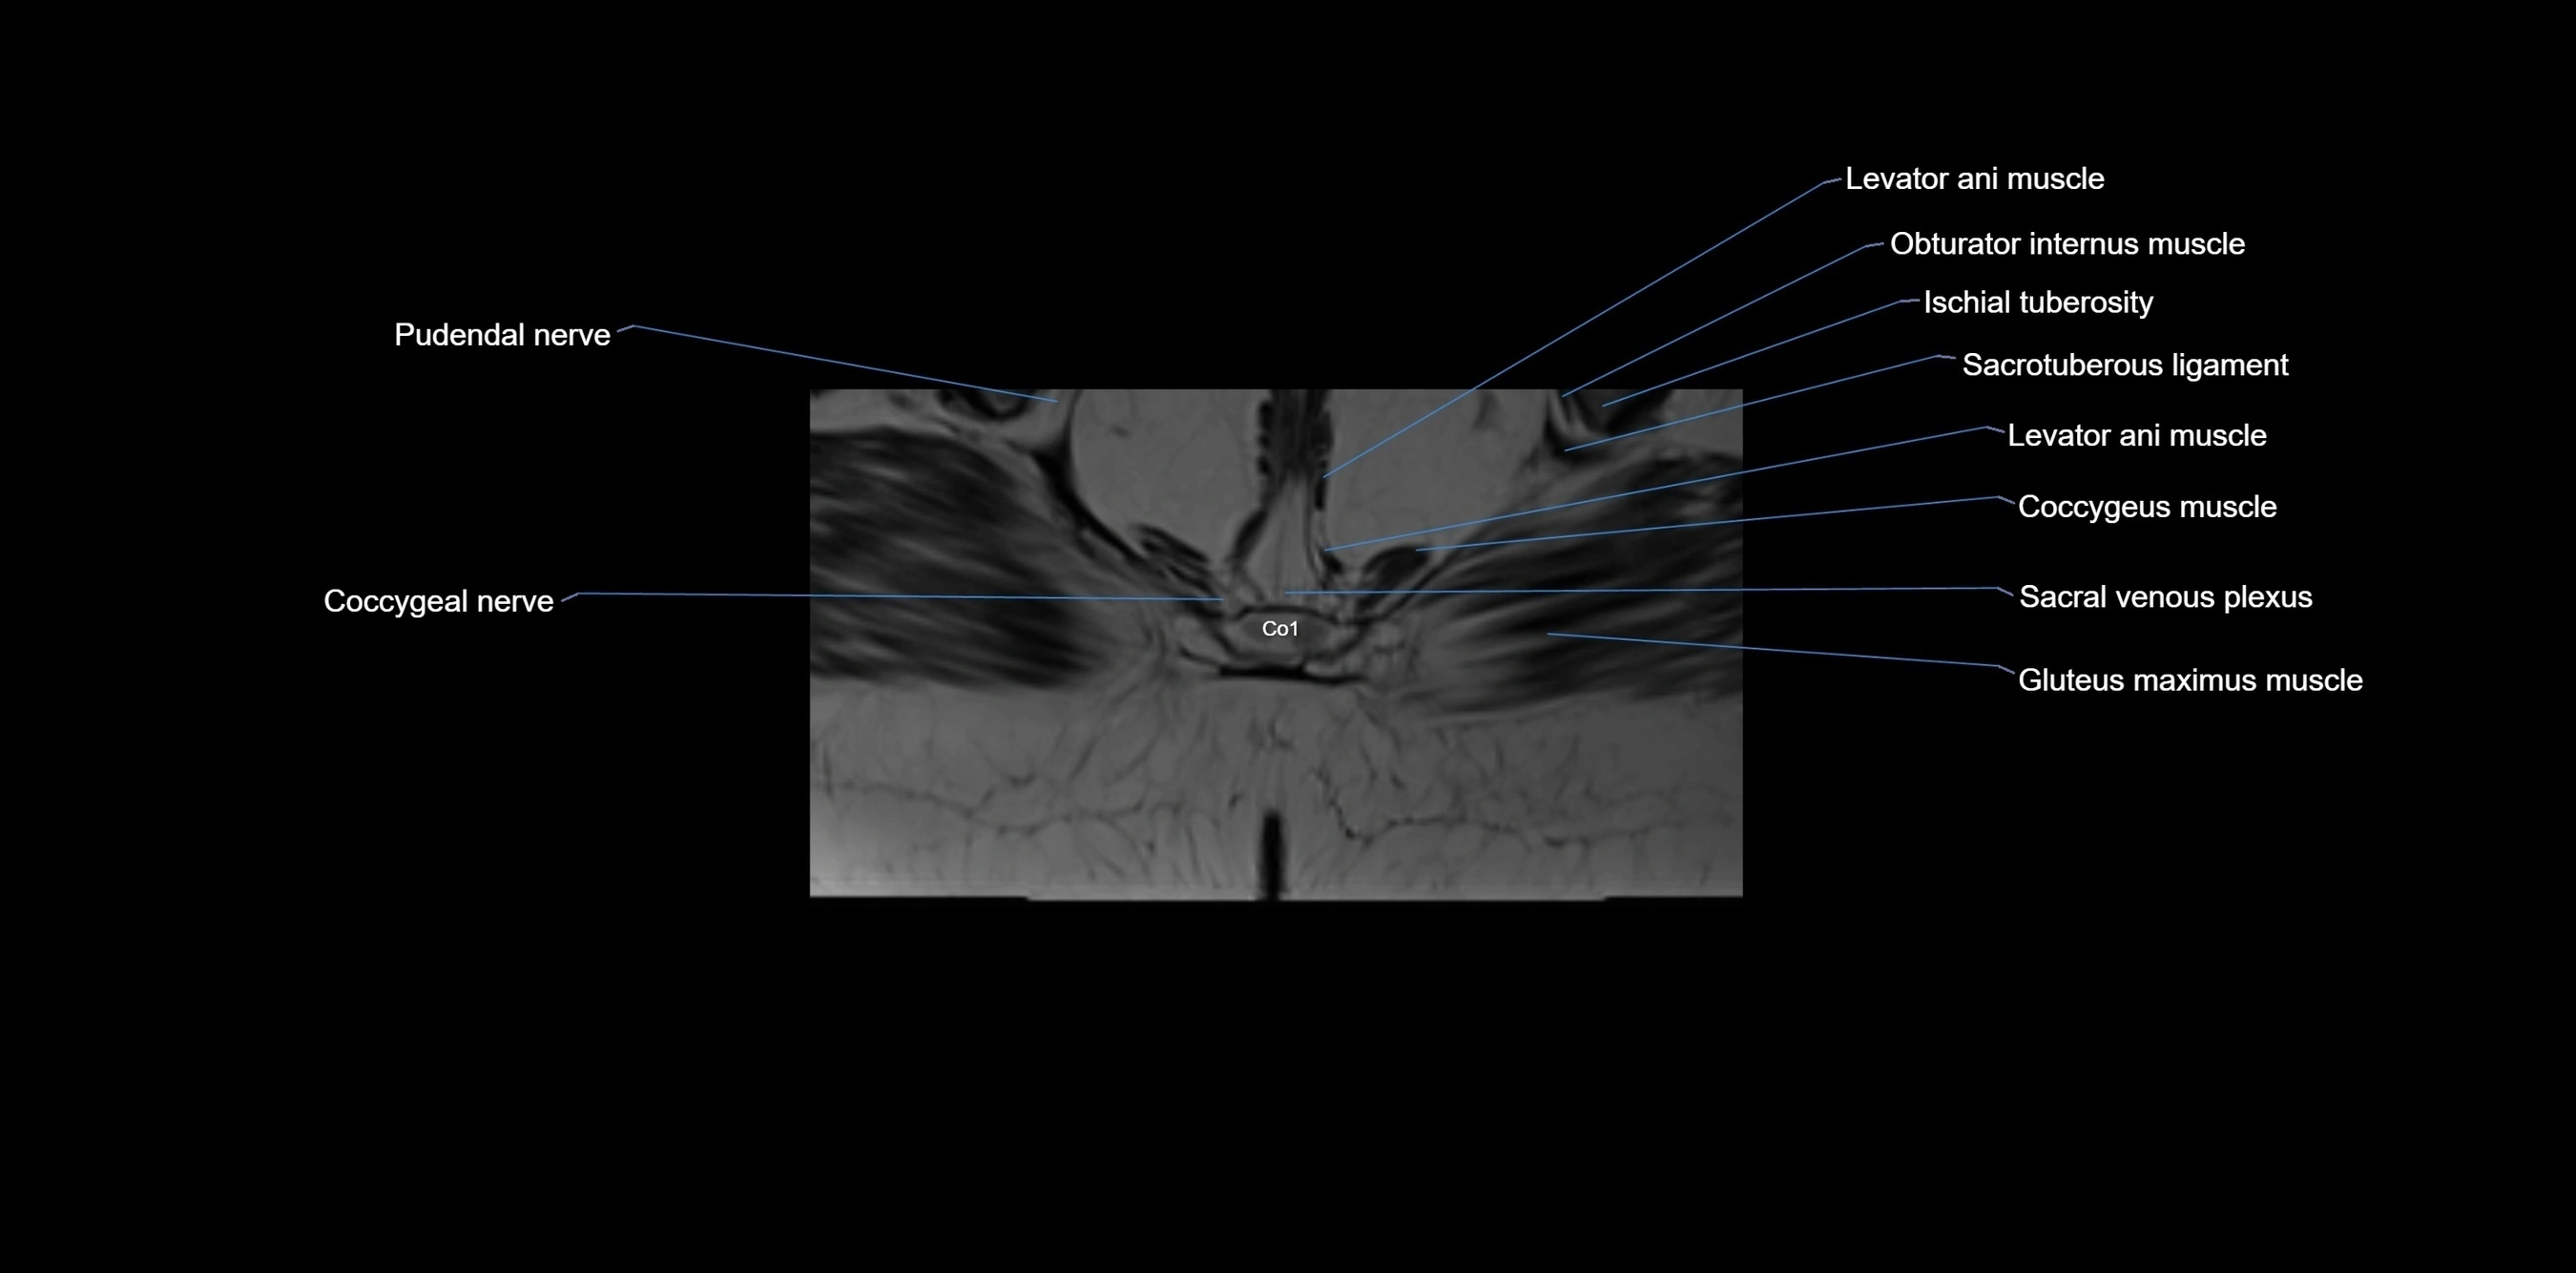

CT image

image